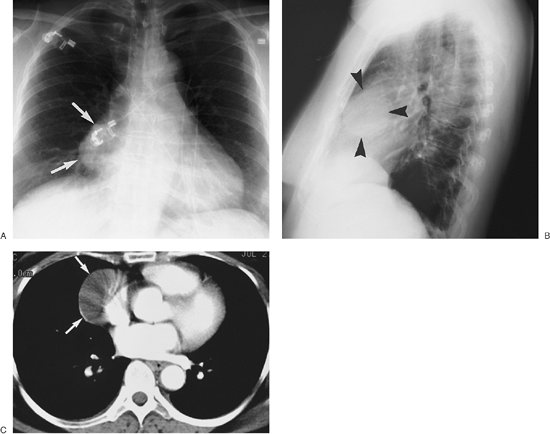

FIGURE 6-34. Pericardial cyst. A: PA chest radiograph shows a smoothly marginated, rounded mass adjacent to the right heart border (arrows). B: Lateral chest radiograph shows the mass to be in the anterior or middle mediastinum (arrowheads). C: CT scan shows a mass of homogeneous fluid attenuation abutting the right pericardial border, typical of the appearance of a pericardial cyst (arrows).